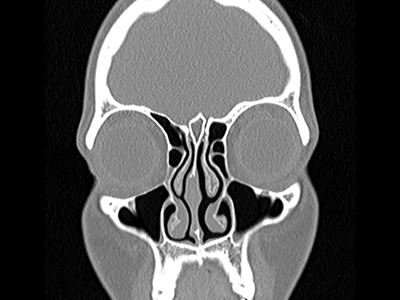

در جراحی زیبایی بینی، حفظ عملکرد تنفسی به اندازه اصلاح ظاهر اهمیت دارد. پیش از عمل، جراح با استفاده از روشهایی مانند آندوسکوپی بینی و تستهای عملکرد تنفسی (رینومانومتری)، وضعیت عبور هوا و سلامت دریچهها را بررسی میکند. در صورت نیاز، سیتیاسکن سینوس نیز انجام میشود تا مسیرهای هوایی و ساختارهای داخلی بینی با دقت ارزیابی شوند.

جراحی زیبایی بینی (رینوپلاستی) تنها با هدف تغییر ظاهر انجام نمیشود؛ یکی از ارکان مهم موفقیت آن، حفظ یا بهبود عملکرد تنفسی است. پیش از عمل، ارزیابی دقیق مسیرهای تنفسی توسط جراح انجام میشود تا هرگونه انسداد، انحراف تیغه یا تنگی دریچههای بینی مشخص شود.

بررسی داخل بینی با آندوسکوپی برای مشاهده دقیق دریچهها و شاخکهای بینی

انجام تستهای عملکرد تنفسی (رینومانومتری) در صورت نیاز برای سنجش جریان هوای بینی

در موارد خاص، سیتیاسکن سینوس و بینی برای بررسی ساختار داخلی انجام میشود

ترکیب دقت در تحلیل زیبایی و ارزیابی عملکرد تنفسی باعث میشود نتیجه نهایی نهتنها از نظر ظاهری طبیعی و متناسب باشد، بلکه تنفس بیمار نیز بهبود یابد و از بروز عوارضی مانند گرفتگی یا تنگی مسیر هوا جلوگیری شود.